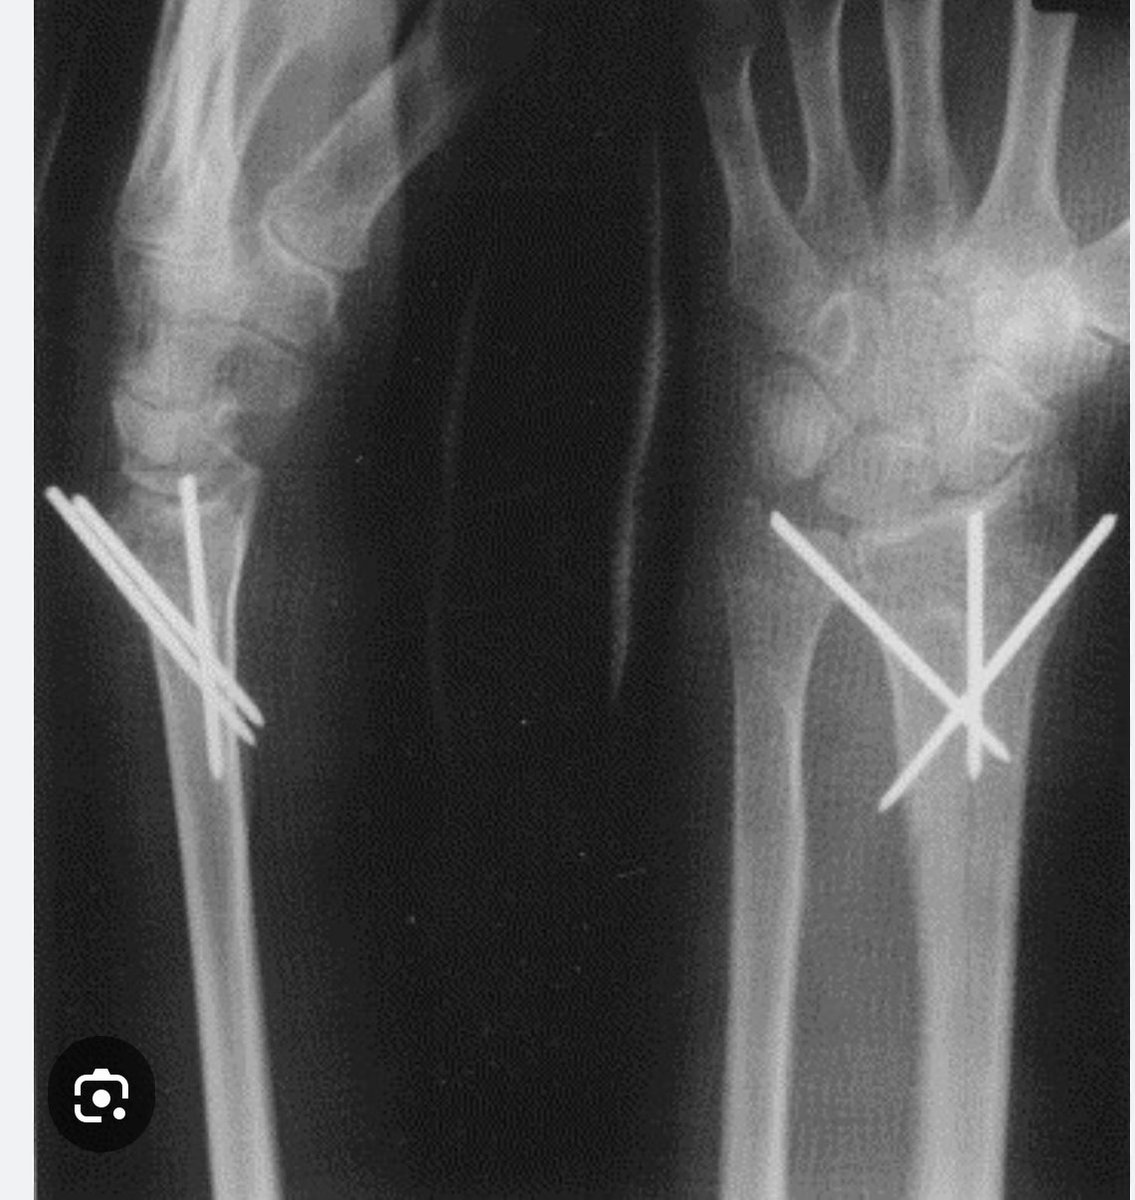

@Gnomelover1970 Can you call it Kapandji pinning technique sir ?

I always cringe a little when i see medial malleolar fixation like this longer does not equal better! in fact, the longer the screw, the more likely youre in the medullary canal and there's literally NO BONE there! most dense bone is at the physeal scar pubmed.ncbi.nlm.nih.gov/24293597/